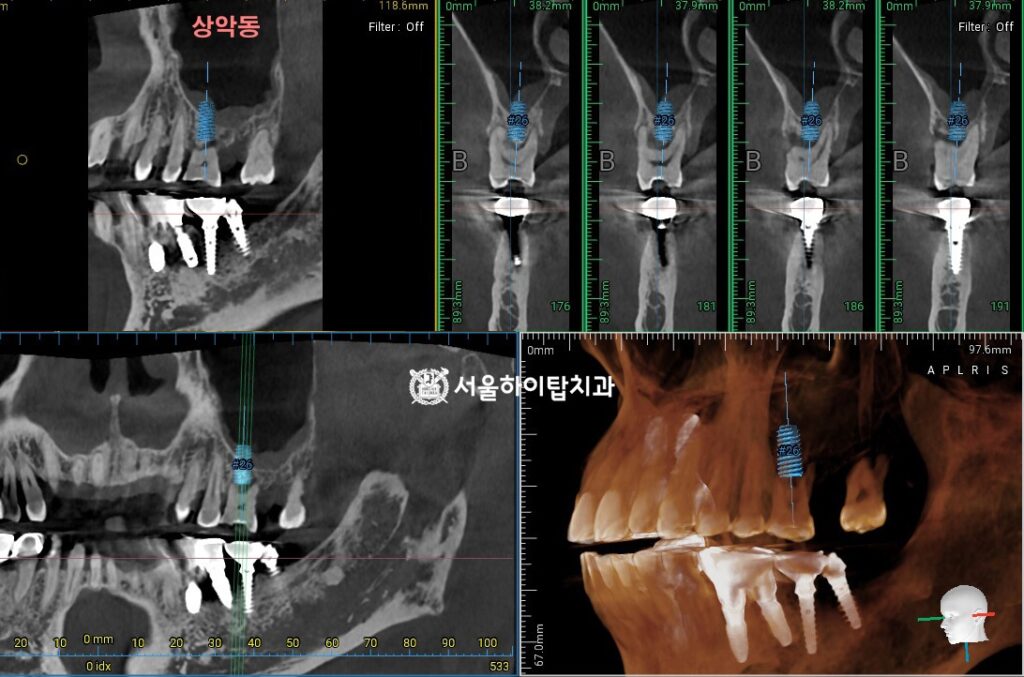

CT 기반 임플란트 식립 가상 시뮬레이션

CT를 기반으로 임플란트 뿌리(픽스처, Fixture)를 가상으로 식립해 보면,

간석역 치과 에서는 잔존 치조골의 양이 매우 부족해 임플란트가

해부학적 구조물인 상악동을 침범할 수밖에 없는 위치에 놓이게 됨을 확인할 수 있습니다.

즉, 임플란트를 지지해 줄 수 있는 뼈가 부족한 상태이기 때문에

상악동 거상술을 동반하여 상악동 바닥을 안전하게 들어 올린 뒤,

임플란트를 지지할 수 있는 공간을 확보하고

부족한 뼈를 보강하는 치료가 고려될 수 있습니다.

이러한 과정을 통해 임플란트가 식립될 수 있는

충분한 골량과 안정적인 환경을 먼저 조성하여

예후가 좋은 임플란트 치료를 진행할 수 있습니다.